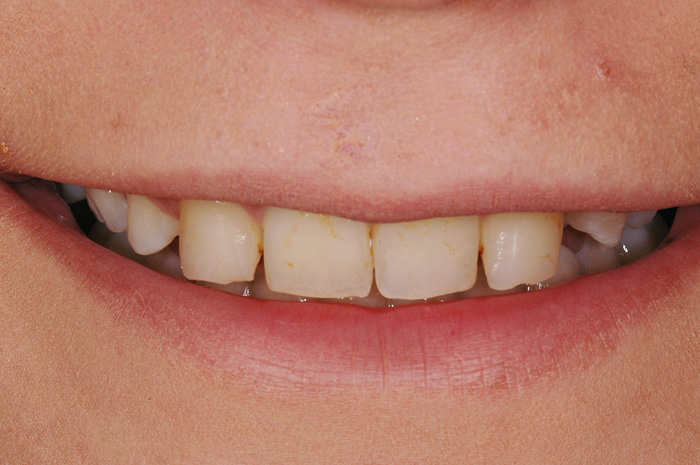

Fallbeispiel

Zum Vergrössern klicken